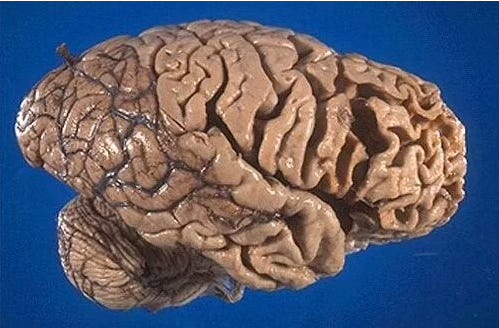

Frontotemporal dementia (FTD) refers to a group of disorders caused by progressive nerve cell loss mainly in the brain’s frontal lobes (the areas behind your forehead) and/or its temporal lobes (the regions behind your ears).

Brain regions impaired in FTD are the ones responsible for self-monitoring, impulse control, and reality-checking. The nerve cell damage caused by FTD leads to loss of function in these brain regions, and in bvFTD, the nerve cell loss is most prominent in areas that control conduct, judgment, empathy and foresight.